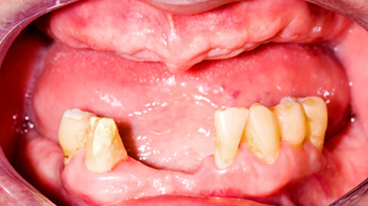

写真のように悪化すると膿みが出てきて強い口臭がし、顎の骨が溶けていき、歯を支えている組織が破壊され、最終的には歯が抜けてしまします。

(食べ物を噛む力が弱くなる・顔貌が変わる)重度の歯周炎になると、歯がグラグラして、歯と接している歯茎がさらに腫れ、化膿が進みます。歯と歯の間が広がり、歯茎が下がって、歯が長く見えます。この段階の治療法は再生療法を用いて歯周組織の再生をはかるかことが多いです。しかし、ここまで進行すると抜歯になる可能性が高くなります。